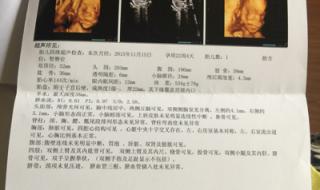

四维B超是系统性排查畸形筛查,是孕期里比较重要的一次检查。而四维B超单里会详细的显示出胎儿各方面发育的情况,而只要结果单上没有显示异常,就代表胎儿是健康的,例如正常胎儿头部轮廓比较清晰;胎儿脑中线无移位、无脑积水和头部畸形的状况;胎儿侧脑室宽度正常值在10mm以下等,都是表示胎儿正常发育。

1、四维彩超检查报告单上会有提示,宝宝发育正常指标,双顶径,头围,股骨长,腹围,侧脑宽度,羊水指数,胎心。这些发育指标长数据表示。

2、1正常的胎心率在120~160每分钟之间,超过这个范围就是不正常的。双顶径和肱骨长,一般都随着孕周的增加而增加。

3、2大多数宝宝肱骨长比双顶径少20~30mm,超过这个范围则属于异常。宝宝侧脑的是的,宽度不能超过10mm,10mm以上都是不正常的4羊水深度在3到8cm之间,羊水指数在8到18cm之间,超过这个范围是异常。